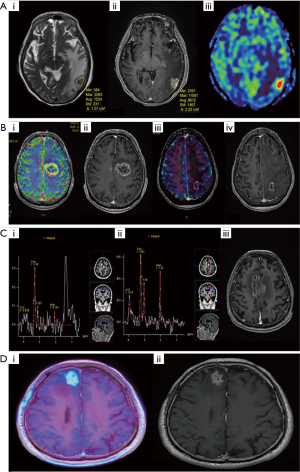

Radiation necrosis may be difficult to distinguish from intra-cranial recurrences clinically and radiologically (55). Clinical signs largely depend on its size/location, or at times may remain asymptomatic. It appears as a contrast enhancing lesion (on T1 sequence) with surrounding edema and changes in signal intensity on MRI brain which is also a common feature of a recurrence (72). Surgical biopsy or resection of enlarging lesions post-SRS seen confirmed radiation necrosis in 22 out of 23 cases (73). Diffusion-weighted MR imaging has been used to distinguish between radiation necrosis and tumor progression (74). Amino-acid tracers (such as Carbon-11 methionine, and Fluoroethyltyrosine) in positron-emission tomography (PET) scanners are particularly useful, as normal brain parenchyma has a relatively lower amino acid uptake (75). For example, FET-PET imaging has been reported to have a sensitivity of 100% and specificity of 93% in the setting of recurrent gliomas (76). Additionally, MRI sequences such as Chemical Exchange Saturation Transfer (CEST) have shown promise in differentiating RN from tumour progression (77). Figure 1 shows the radiological features of RN seen on various imaging modalities and comparison with tumour progression (78).